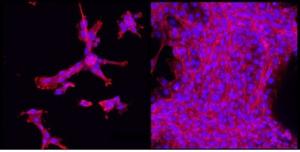

» Vous pouvez ajouter un colorant fluorescent, un peptide ou une protéine et vous pouvez le fabriquer en une minute « . Enfin, l’hydrogel Clic alginate est robuste et résiste à la dégradation prématurée et à l’invasion par les tissus environnants. Sur le visuel de gauche, on voit que l’hydrogel sur la droite (espace blanc) reste intact après injection dans le tissu sous-cutané (à gauche), la limite entre l’hydrogel et le tissu environnant apparaissant en orange.

L’application en ingénierie tissulaire : Au Wyss Institute, le nouvel hydrogel est déjà utilisé pour encapsuler des cellules en culture et tester la réparation tissulaire, mais aussi les mouvements cellulaires lors de la cicatrisation. Le matériau est décrit ainsi non seulement comme prometteur pour les applications d’ingénierie tissulaire, pour la délivrance de médicaments, mais aussi pour la culture cellulaire et la recherche.